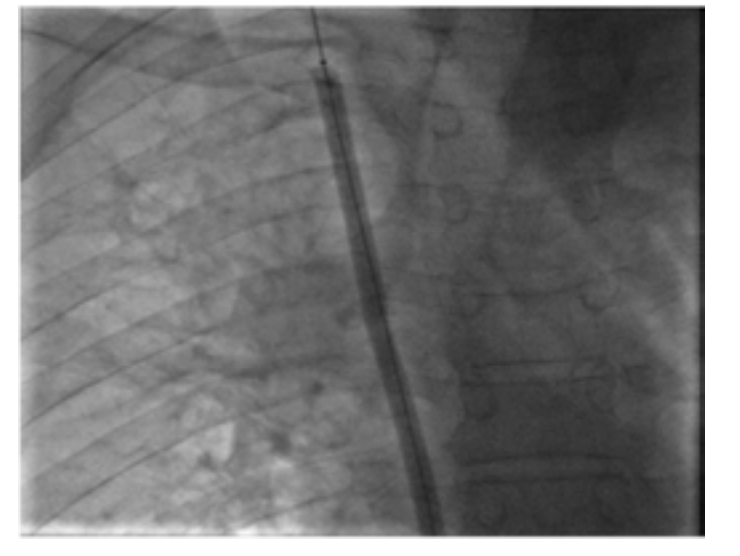

From a therapeutic point of view, endovascular treatment of SVCS had been performed under local anesthesia. Percutaneous vena femoral approach was carried out in 2 cases. Three patients also required the use of the basilica pathway. Before stenting, the caval stenosis was dilated two or three times for almost 10 minutes by means of balloon inflation to the estimated diameter in three cases. We also routinely performed post-stent dilatation. In all procedures, a self-expanding stent had been deployed. The details regarding the stent deployed are summarized in Table 1. As an immediate follow-up, the patients experienced a quick relief of symptoms between 48-72 hours.